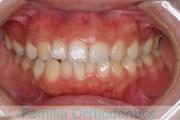

下の前歯が後ろにあるのが気になるとのことで来院されました。非抜歯で行うことも可能でしたが、上下左右から小臼歯抜歯をして治療を行うことをご希望になりました。

マルチブラケット法にて治療を行い、約3年、40回の通院が要でした。

かみ合わせが深い(上の前歯で下の前歯が覆われてしまう)ので、保定をしっかりしないと、また深くなってきてしまいやすいです。

- ≫治療後

-

上顎

下顎

前歯の関係など

右側

正面

左側